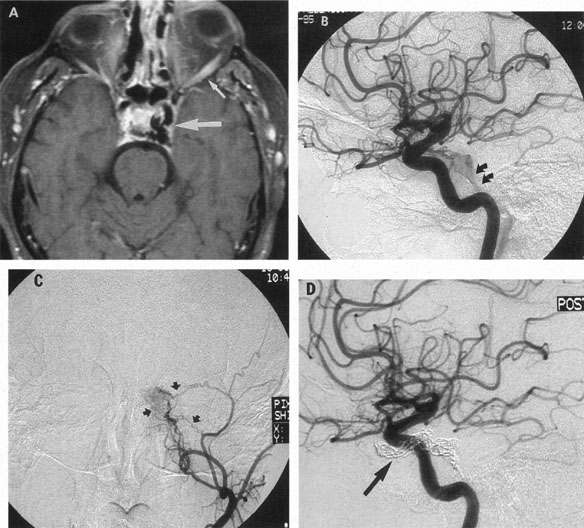

Aneurysms that primarily arise form the carotid system at the origin of the posterior communicating artery are of special interest to neurologists, neurosurgeons, and ophthalmologists because they tend to involve the oculomotor nerve. The classic presentation is sudden onset of severe unilateral frontal headache, ptosis, limitation adduction, depression and elevation of the eye, and dilated and fixed pupil. The cerebrospinal fluid is grossly bloody, and angiography is diagnostic (Fig. 5). Pain in and around the eye in the trigeminal–ophthalmic distribution is a conspicuous symptom, but sensory defects are absent. Clinical and pathologic evidence indicates that impairment of function by a contiguous aneurysm usually occurs in conjunction with hemorrhage into the oculomotor nerve that, along with sudden distortion, can produce referred pain.27

Fig. 5. Aneurysm at the junction of the internal carotid and posterior communicating arteries. A: Contrast-enhanced axial computed tomography (CT) shows a large aneurysm (arrows). Magnetic resonance imaging (MRI) studies effectively demonstrate the aneurysm. B: T1-weighted MRI with gadolinium. C: T2-weighted (arrow indicates black flow void). D: Selective internal carotid angiogram. E: Magnetic resonance angiogram (MRA; curved arrow) shows the same aneurysm. F: Helical image-intensified CT technique provides quasi-three–dimensional mold of arteries: 1. right posterior cerebral; 2. posterior superior cerebellar; 3. basilar; 4. internal carotid; 5. posterior communicating; 6. left posterior cerebral; 7. supraclinoid aneurysm, same as depicted in A through E. (Courtesy of Dr. Raphael Aponte.)